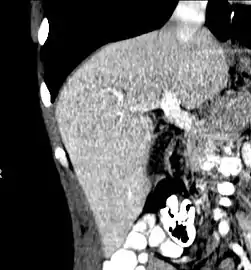

Axial CT image showing anomalous hepatic veins coursing on the liver's subcapsular anterior surface[66]

Axial CT image showing anomalous hepatic veins coursing on the liver's subcapsular anterior surface[66] Maximum intensity projection (MIP) CT image as viewed anteriorly showing the anomalous hepatic veins coursing on the anterior surface of the liver

Maximum intensity projection (MIP) CT image as viewed anteriorly showing the anomalous hepatic veins coursing on the anterior surface of the liver Lateral MIP view in the same patient as previous image

Lateral MIP view in the same patient as previous image A CT scan in which the liver and portal vein are shown

A CT scan in which the liver and portal vein are shown